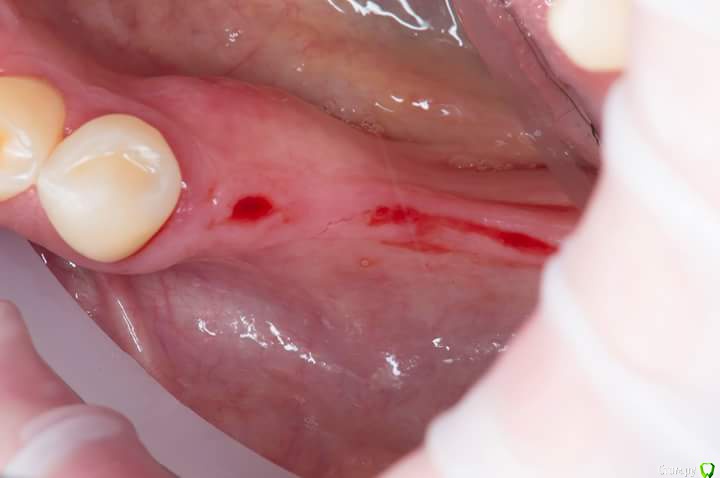

Sampson Опубликовано 13 июля, 2018 Автор Поделиться Опубликовано 13 июля, 2018 Вид через 7 дней.Не болит, нет отека.Швы на 45 46 тугие.при подтягивании безболененые и кровоточат. Ссылка на комментарий

Sampson Опубликовано 7 августа, 2018 Автор Поделиться Опубликовано 7 августа, 2018 месяц спустя Ссылка на комментарий